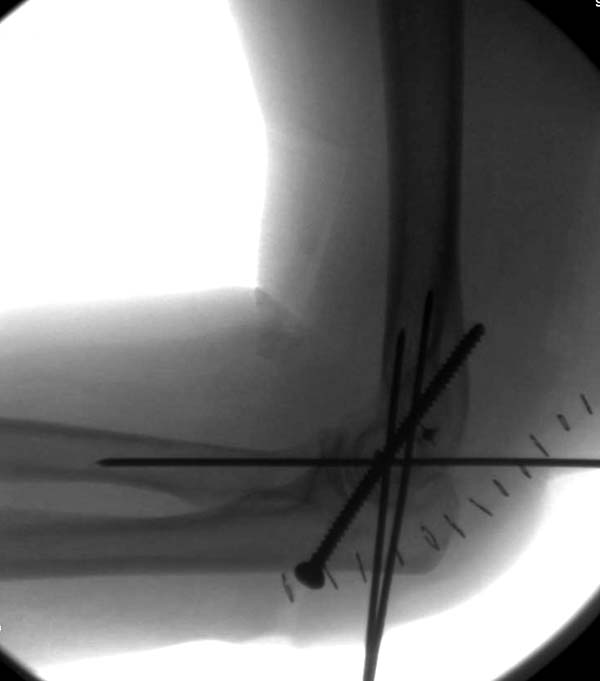

Несмотря на отрицательный отзыв, некоторые нестабильные вывихи лечим трансартикулярным методом. Тонкие спицы ломаются и имеют риск внутрисуставной инфекции. Винты 3.5 мм не выдерживают, а более толстые каннюлированные винты неплохо проявили себя. Неосторожность при установке приводила к поломке тонких guide wire внутри сустава. Лучшие кортикальные в 4.5 мм и гипс на три недели. Винт удаляется, затем разработка сустава.

Иногда гипс не гарантировал стабильность и винт внутри гипса ломался. Удаление сломанного винта облегчаем, оставляя на пару мм длиннее с наружной стороны, Т.е винт через олекранон над наружный мыщелок, и никогда в трубку диафиза! Из малого разреза кончик сломанного винта удаляется без проблем.

Для примера здесь случай начатый в другом центре, а потом переправленный к нам.

Снимки: 1-2 вывих, 4-5 вторичное смещение в гипсе, реконструкция латеральной связки и капсулы 13-14, повторный вывих после реконструкции, перевод в наш центр; 18-21 временная фиксация, 22-25 трансартикулярная фиксация и нестабильная головка фиксирована спицами, 29-30 амбулаторно, 32-33 после удаления винта и спиц...